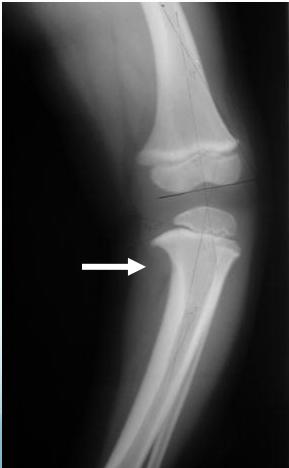

Indications: X-ray when severe or possibly pathologic

Recommended Views:

- Standing AP film: Long film (hips to ankles) with patellae directed forwards

Radiological Parameters to Assess:

- Medial Physeal Slope

- Femoral-Tibial Axis

Tibia vara (Blount’s disease)

Medial Physeal Slope

Femoral-Tibial Axis